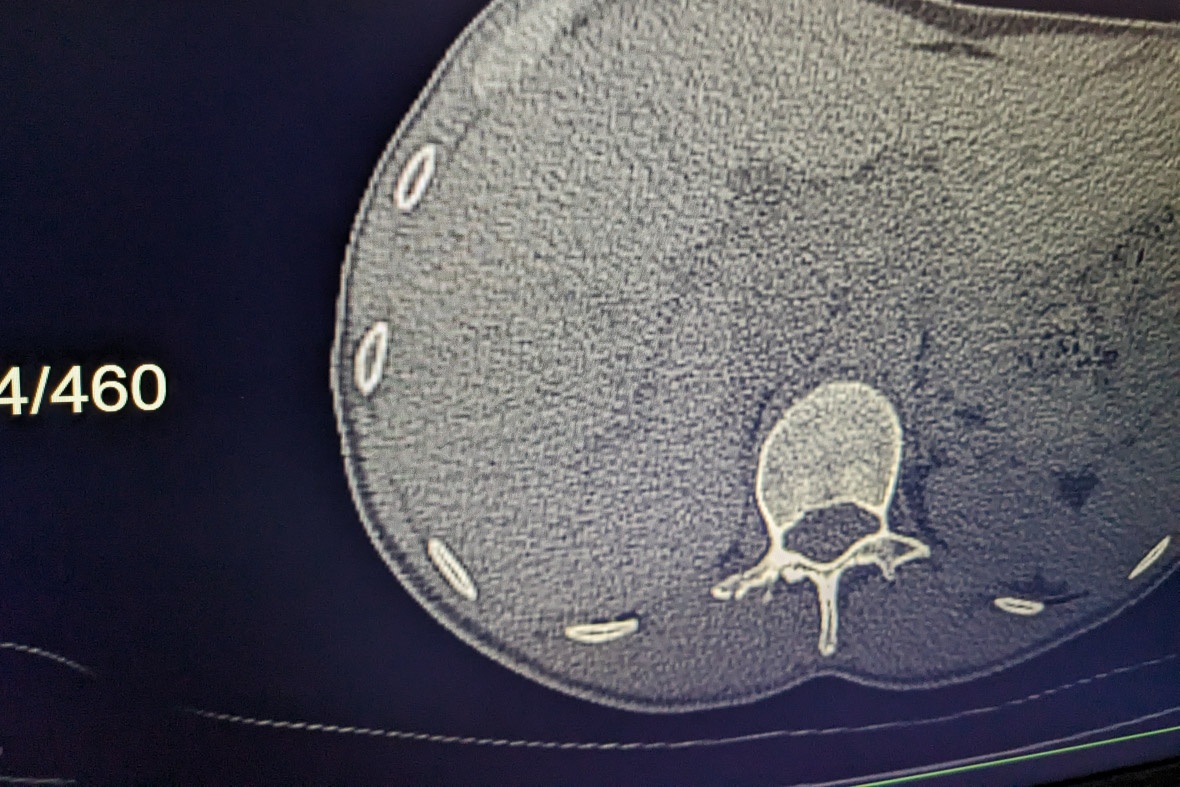

A sürgősségin jól ellátták. Szakmailag nem értek hozzá, de emberileg minden rendben volt. Semmi panaszunk nem lehet, azon kívül, hogy engem 4-5 órát várakoztattak egy töksötét váróteremben, egy hatalmas oxigénpalack társaságában. De az asszonnyal jól bántak, mindent kivizsgáltak. Ultrahangos vizsgálatot nem tudtak végezni, mert nem volt szakemberük, de végeztek helyette CT-t. Találtak egy törött csigolyát, és csúnya zúzódásokat, amelyeket ki kell heverni.